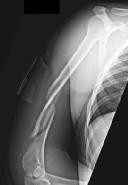

Question 53

A 55-year-old male presents with deep, aching pain in his proximal humerus. Radiographs demonstrate a large, permeative lytic lesion with intralesional 'popcorn' calcifications and significant endosteal scalloping. Core needle biopsy confirms a Grade II (intermediate grade) chondrosarcoma. What is the standard treatment of choice for this lesion?

Explanation

Conventional chondrosarcomas are generally resistant to both chemotherapy and radiation therapy. The standard of care for Grade II and Grade III chondrosarcomas is wide, en bloc surgical excision. Extended intralesional curettage with local adjuvants is generally reserved for low-grade (Grade I/atypical cartilaginous tumors) in the appendicular skeleton.